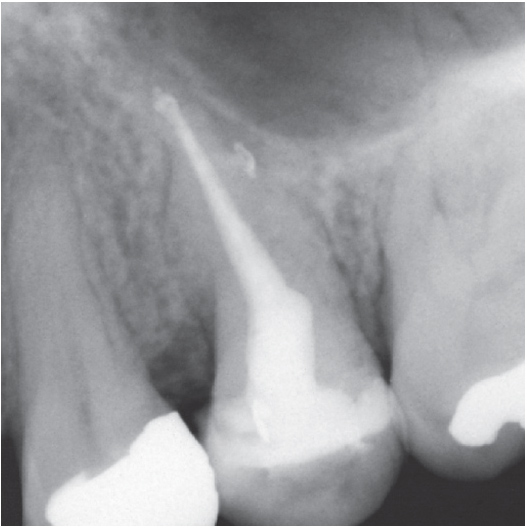

After

After Root Canal treatment